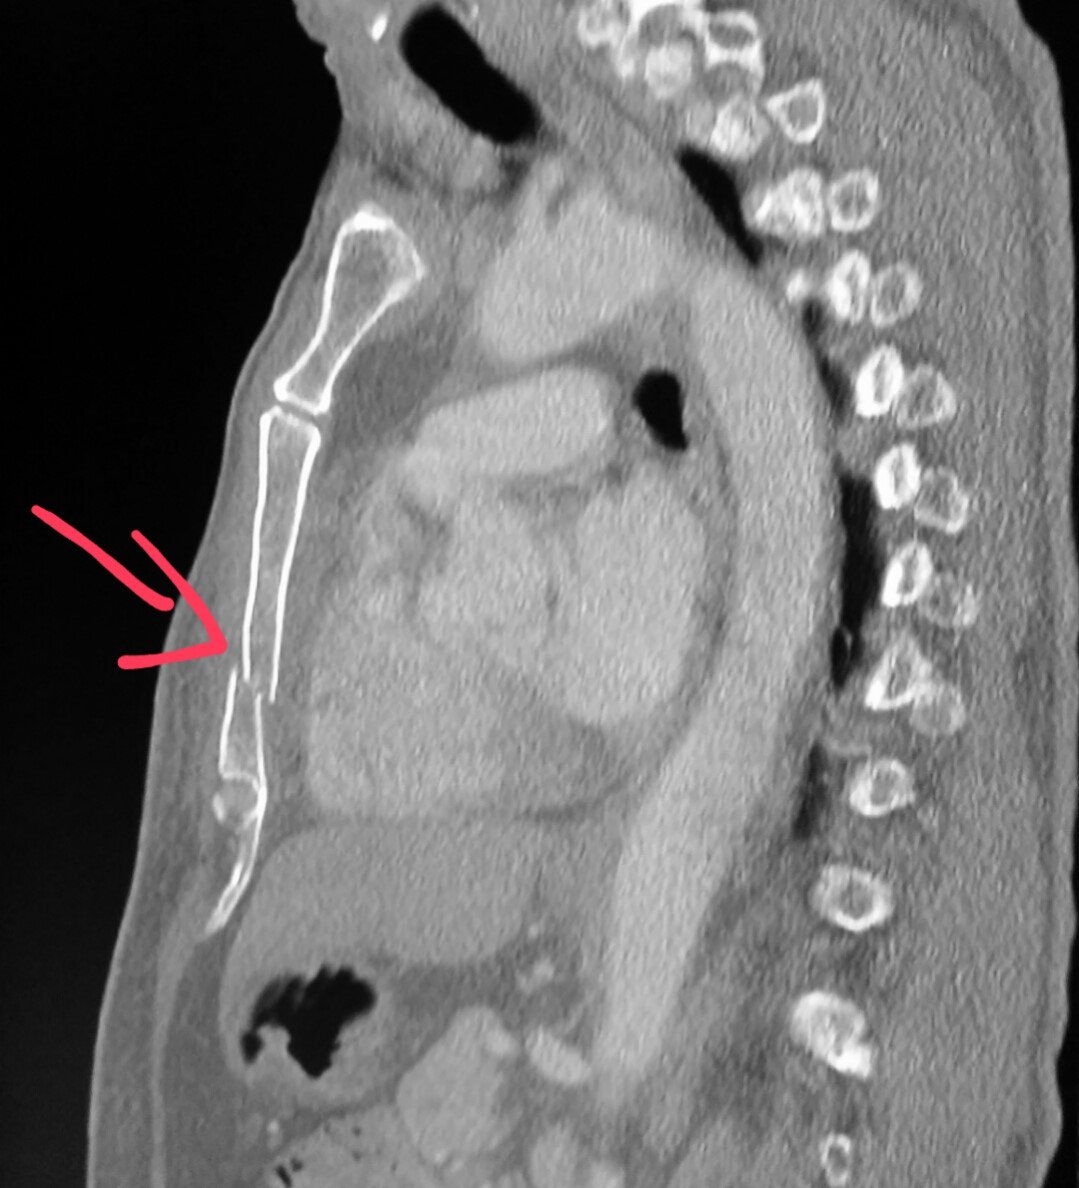

Nbrowardradiologists On Twitter Chest Ct Scan Side View Shows A Broken Breastbone Sternum Man W Chest Pain After Car Accident Pain Trauma Mva Injury Https T Co Qqywdiegjm Twitter